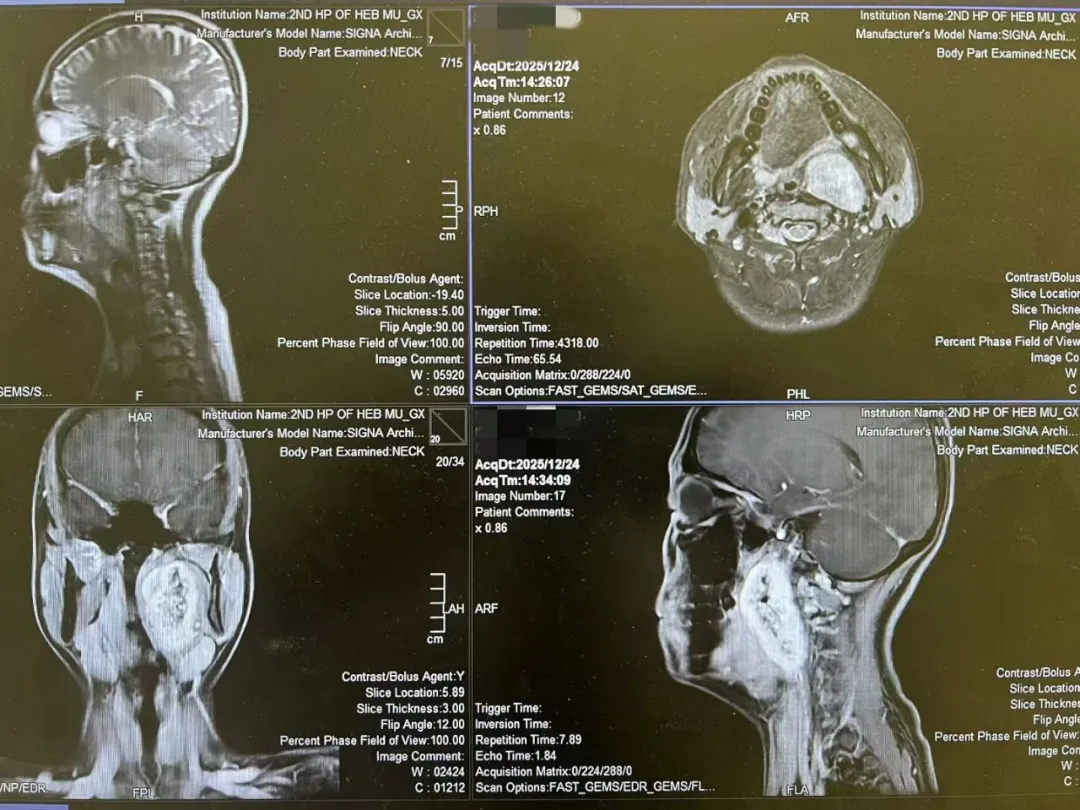

一台经口入路咽旁间隙巨大肿物切除术后的随笔 今天,完成了一台有些特别的手术。 患者是一位年轻的女孩,咽旁间隙,七厘米的巨大肿物。像一颗沉默的炸弹,深藏在颈侧的重重屏障之后——...